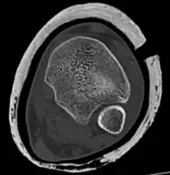

صورة شعاعية سريرية / صورة عظمية

بعد ذلك، أظهرت الأشعة السينية الأولية كسرًا في الجزء الأنبوبي من قصبة الساق والشظية، مصنفًا حسب نظام AO/OTA 42B. عند الفحص الدقيق، اشتبه بوجود خط كسر يمتد إلى مفصل الكاحل.

للتأكد من امتداد الكسر، تم إجراء فحص بالأشعة المقطعية (CT) للجزء السفلي من قصبة الساق، والذي كشف عن كسر إضافي غير متبدل في الجزء الخلفي من قصبة الساق عند مستوى مفصل الكاحل.